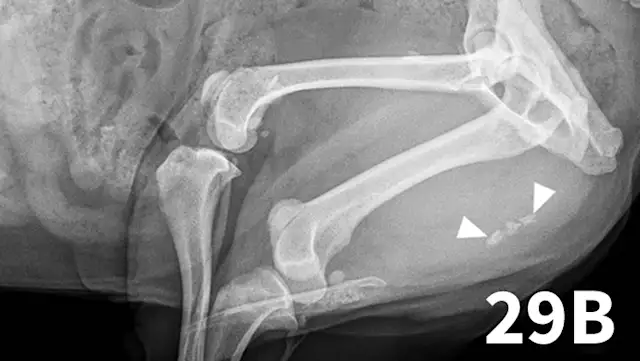

The normal urethra of dogs and cats is difficult to visualize on survey radiography and ultrasonography. Radiopaque urethroliths can be observed on survey radiographs, and therefore the entire urethra should always be included in the field of view (Figure 28). In male dogs, it is useful to pull the hindlimbs forward to assess the urethra between the pelvis and os penis (Figure 29). The prostate gland and proximal urethra, before entering the pelvic canal, can be visualized with ultrasonography, especially if there is urethral distention. In male dogs, the urethra at the proximal os penis can be evaluated with ultrasonography to assess for urethroliths, which commonly lodge in this location. Positive-contrast retrograde urethrography is the best tool for diagnosis of intraluminal, intramural, and extramural compressive urethral disorders as well urethral rupture (Figure 30).